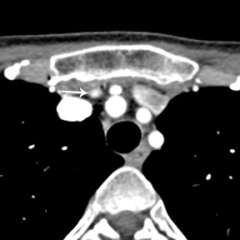

Axial 4D-CT image showing parathyroid adenoma

Axial 4D-CT image showing parathyroid adenoma in the upper chest, behind the sternum (breastbone).